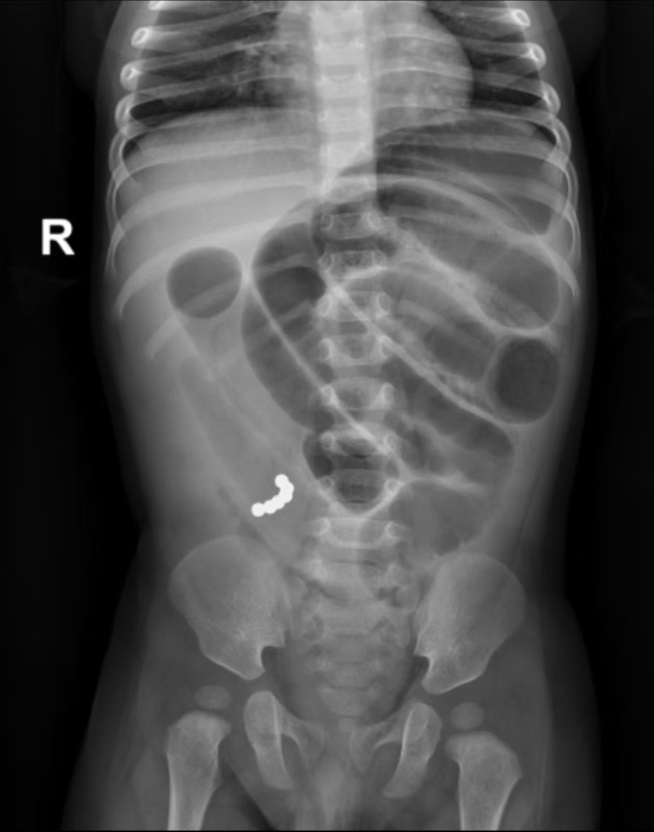

磁力珠异物致肠梗阻